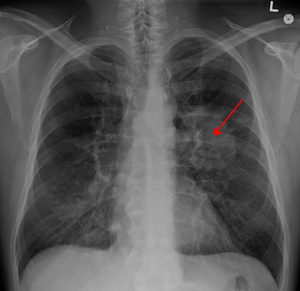

Un estudio interCIBER determina que existe un aumento en la actividad metabólica y una respuesta inflamatoria en el tejido tumoral del cáncer de pulmón no microcítico

El estudio establece que existe un aumento en la actividad metabólica y una respuesta inflamatoria en el tejido tumoral del cáncer de pulmón no microcítico, y una relación significativa entre los niveles elevados de IL1β en el tumor y el mal pronóstico en el adenocarcinoma, abriendo con ello nuevas vías de intervención terapéutica.